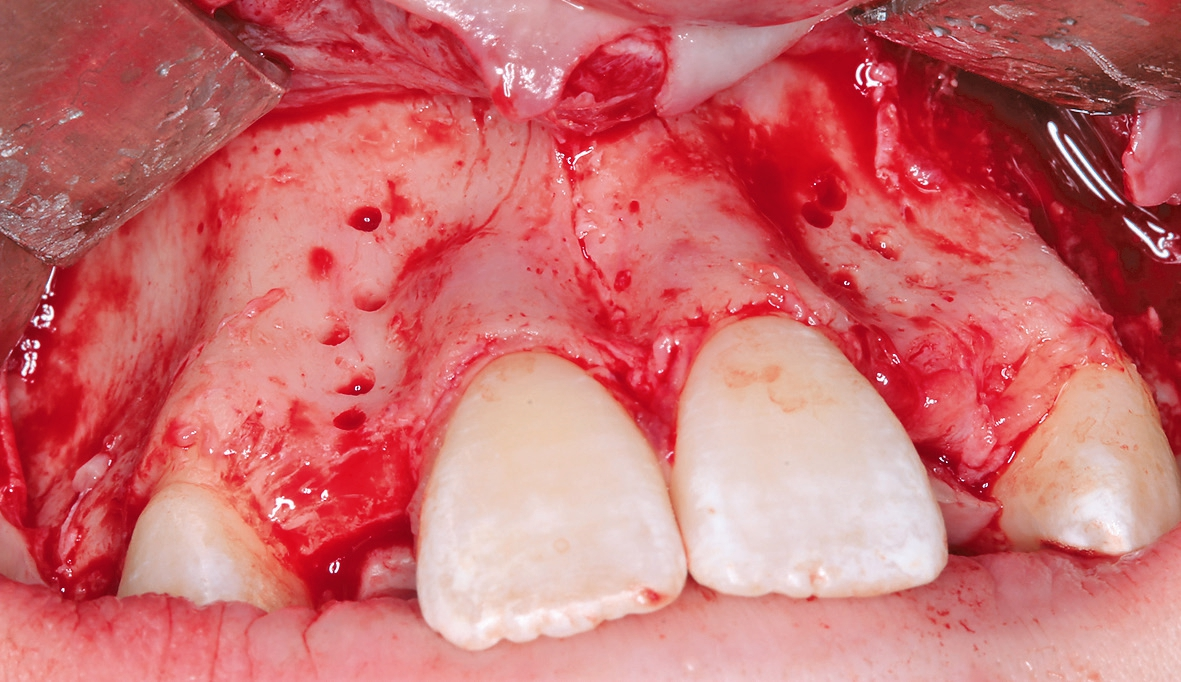

Eine 17-jährige Patientin wurde an unsere Praxis mit dem Wunsch nach einer festsitzenden implantatprothetischen Versorgung der lateralen Schneidezähne 12 und 22 überwiesen. Nach entsprechender Aufklärung und intensiver Beratung wurde zunächst ein DVT erstellt, um das genaue Ausmaß der dreidimensionalen Knochenresorption in regio der fehlenden lateralen Schneidezähne regio 12 und 22 beurteilen zu können. Die röntgenlogische Auswertung ergab eine hochgradige horizontale Alveolarfortsatzbreite von knapp 3 mm in regio 12 respektive von knapp 2,5 mm in regio 22 mit stark ausgeprägter konkaver Kontur der bukkalen Lamelle (Abb. 1). Allein das klinische Bild (Abb. 2 und 3) zeigte eine ausgeprägte horizontale Alveolarfortsatzatrophie in regio 12 und 22 mit ausgeprägten Konkavitäten in der bukkalen Lamelle.

Letztendlich bestand aus kieferorthopädischer Sicht keine Kontraindikation für eine unverzügliche chirurgische Intervention mit nachfolgender implantatprothetischer Versorgung bei derart fortgeschrittener horizontaler Atrophie in regio 12 und 22 (2,5 mm mit großer Konkavität). Insofern wurde nach erneuter intensiver dokumentierter Beratung und Aufklärung wie auch wirtschaftlicher Aufklärung nach entsprechender beidseitiger Leitungsanästhesie am Foramen infraorbitale und zusätzliche intraoralen und vestibulären Infiltrationsanästhesien zunächst ein breiter Mukoperiostlappen von regio 14 bis 24 gebildet (Abb. 4) und zur Förderung der Durchblutung des allogenen Transplantates wurden entsprechende Bleeding-Points (entsprechende Perforation der bukkalen Kortikalis) gesetzt (Abb. 5). Die mit Hilfe von CAD/CAM durch das Labor ProDent (Zahntechnikermeister Thomas Blaschke) hergestellten kortikospongiösen Blöcke nach DVT-Auswertung wurden mit entsprechenden Osteosyntheseschrauben fixiert (Abb. 6) und mögliche Restspalträume mit allogener Spongiosa abgedichtet und lateral auskonturiert.